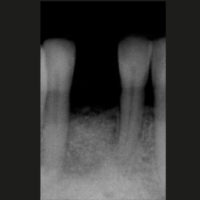

- Figg. 1, 2 – Monoedentulia del 41 a 5 mesi dalla ridge preservation. Il sito rigenerato mostra una distanza bucco-linguale idonea all’inserimento di un impianto anche di diametro standard. La distanza interdentale è però fissa. Un diametro implantare ridotto aumenta la distanza dente-impianto favorendo la formazione della componente trasversale della ampiezza biologica

- Fig. 2

- Figg. 3, 4 – Finalizzazione della riabilitazione implanto-protesica della monoedentulia 41. Integrazione estetica e funzionale della protesi. Il biomateriale è in via di organizzazione

- Fig. 4